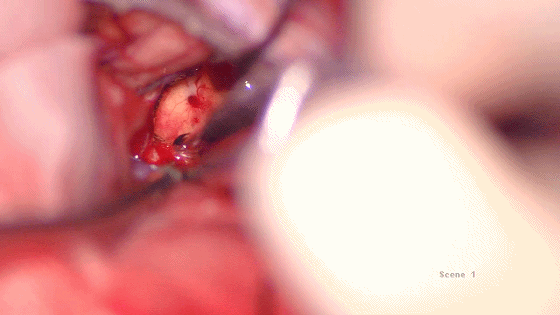

肿瘤完全切除后见脑干背面

三脑室底部

三脑室后部